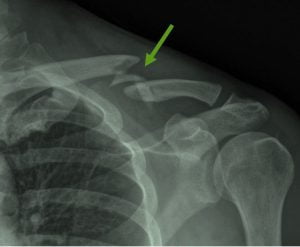

שבר בקלביקולה – שבר בעצם הבריח אוקטובר 16, 2022 אין תגובות שבר בקלביקולה / שבר בעצם הבריח, ברוכבי אופניים תחרותיים – תוך כמה זמן חוזרים לרכב? קרא עוד »